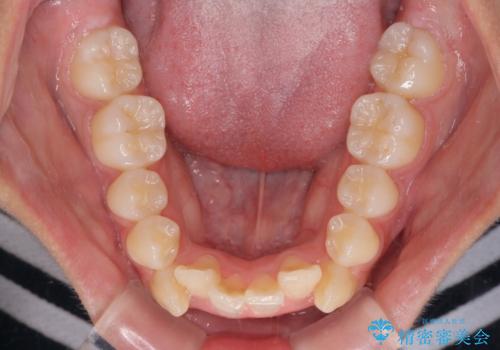

- 歯列全体の叢生を気にして来院された患者様です。

検査を行った結果、上顎骨の横幅が相対的に狭いことが分かり、叢生が強いことから、急速拡大装置にて上顎骨を側方に拡大することで、叢生の解消と奥歯の咬み合わせ改善を図ることとしました。

一般的には上下左右の第一小臼歯4本を抜歯する必要がありますが、拡大量によっては非抜歯矯正の適用となる可能性があるため、まずは非抜歯矯正で治療を開始し、抜歯が必要と判断された時点で速やかに4本抜歯を行うこととしました。